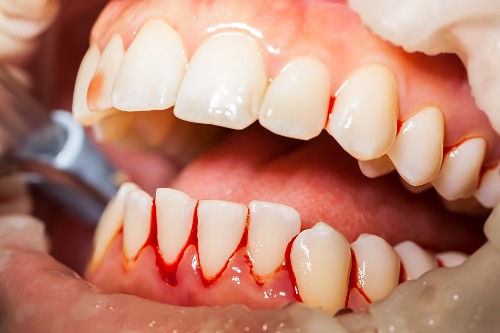

Diş eti kanaması, diş etlerinde aşırı miktarda plak birikmesi nedeniyle başlar. Plak birikimi neticesinde ortaya çıkan renksiz ve yapışkan bir bakteri plağı olan gingivitis, diş etlerinde iltihaplanma oluşumuna sebep olur. Söz konusu plaklar ise zaman içerisinde kanamalara ve sağlıksız diş etlerine neden olmaktadır. [caption id="attachment_8917" align="alignright" width="350"]

diş eti kanaması neden olur[/caption]